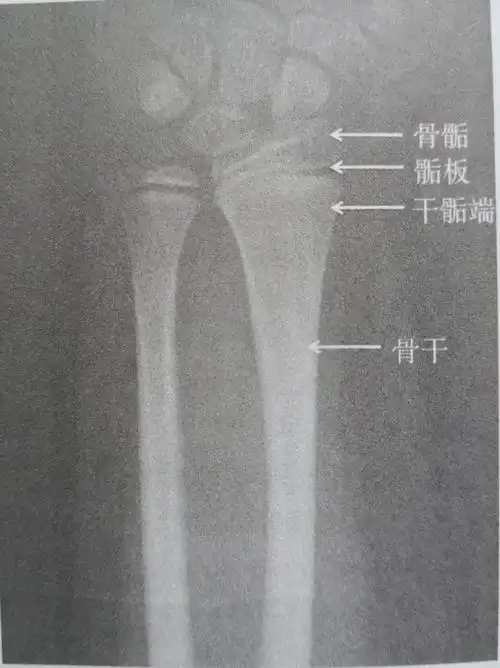

x 线中骨与骨之间的一道间隔就是骨骺线未闭合前的形态.

二,什么是骨骺线闭合 骨骺线是指长骨干骺端与骨骺之间的一层裙骨

儿童的长骨分为四个区域,包括骨骺,骺板(即生长板),干骺端,骨干.

发现这些变化:在第五掌骨,第一节远指骨骨骺,骨干之间缝隙确实比3个月